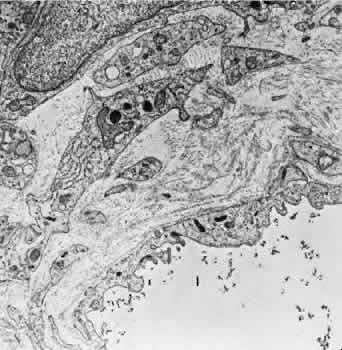

In the retrolaminar zone, the contribution of the choroidal vessels is less. The peripheral aspects of the postlaminar optic nerve are supplied by the pial vessels, whereas the central portion is fed by the axial vessels off the CRA. The afferent channels derived from the short PCAs that cross the border tissue of Elschnig at the level of the choroid have a diameter ranging from 10 to 17 μm.36,37 They quickly branch into a tridimensional vascular network with a polygonal capillary bed. The capillary bed is nonfenestrated, with tight junctions. Numerous pericytes surround the endothelial cells. The capillary mesh measures from30 × 50 μm to 50 × 80 μm, and there are multiple arterial feeding points into the meshwork. The density of the meshwork seems equal in all disc quadrants. Although the capillary bed of the optic nerve head is derived mostly from posterior ciliary vessels, it more closely resembles the retinal capillary bed morphologically than the choriocapillaris. The major efferent vessel for this area of the optic nerve is the CRV. Some of the prelaminar drainage may be through the choroid as well. Direct communications between the CRV and choroidal veins may exist as a result of CRV obstruction or as anatomical variants, which would make the eventual drainage system the vortex veins. The surface capillaries of the optic disc are derived from the retinal vessels.35,37 They anastomose with capillaries of the retina. The prelaminar, choroidal-derived vessels may contribute somewhat to the surface capillary supply. The postcapillary venules that drain the RPC system cross over the disc margin to join with larger venules of the CRV system. It may be these terminal endings of the RPC that bleed with papilledema and other causes of disc swelling. The blood flow to the optic nerve head appears to be under local autoregulatory control.38–40 This flow pattern is similar to the retinal circulation. The site of the autoregulation is not clear; however, both endothelial cells and pericytes probably have a role. The clinical appearance of optic nerve blood vessels in various pathologic conditions has been the focus of intense interest. Alterations in optic nerve blood vessels associated with advancing glaucoma have been an area of particular study in light of the theories concerning a vascular origin for the disease. Quigley and colleagues41 noted that the density of optic nerve head capillaries did not appear to change with worsening glaucoma and that eventual loss of capillaries was in proportion to the accompanying loss of neural tissue. Jonas and associates42 showed that the diameter of parapapillary retinal blood vessels was smaller in eyes with advanced glaucoma than in eyes without glaucomatous damage. This finding appears to represent an autoregulatory response of the retinal and optic disc vasculature to the local loss of retinal ganglion cells and nerve fiber layer. This study confirms an earlier report showing a significant decrease of RBF to the retina in eyes that had undergone inner retinal degeneration.43 CHOROID The choroid is by far the most vascular portion of the eye and by weight is one of the most vascular tissues in the body.44 More than 80% of all ocular blood flow goes to the choroid. The choroidal circulation is responsible for the nourishment of the photoreceptor/retinal pigment epithelium (RPE) complex. Despite these facts, the choroidal circulation has received relatively little attention for two reasons. First, it is difficult to visualize the choroidal vessels directly, and second, there are relatively few pathologic conditions that have unequivocally been associated with a primary deficiency in choroidal circulation. Choroidal blood flow can be assessed in a qualitative manner with fluorescein angiography. The rapidity of choroidal filling, the normal permeability of the choriocapillaris, and the normal blockage of fluorescence as a result of the RPE impede the identification of choroidal perfusion defects. When present, the clinical significance of choroidal perfusion defects on fluorescein angiography is not always clear, either. Newer methods used to study choroidal perfusion more quantitatively include indocyanine green angiography and color Doppler ultrasonography.45,46 Indocyanine green angiography in particular has made the choroid more accessible to clinical evaluation and interpreting the role of the choroid in various disease entities. Along with its paramount task of providing nutrition to the outer retina and RPE, the choroidal circulation also has other roles. It serves as a heat sink, removing the large amount of heat that develops as a result of the metabolic processes initiated when photons strike the photopigments and RPE.47 In addition, the choroid itself probably serves as a mechanical cushion for the internal structures of the eye. The overall structure of the choroidal circulation is segmental.47–52 This segmental distribution of blood begins at the level of the posterior ciliary branches and is mirrored in the vortex vein drainage system. Because of the segmental distribution, the large and medium-sized choroidal arteries act as end arteries. Unlike most other tissues, in the choroid the large vessels do not run parallel to each other. The segmental distribution of blood flow to the choriocapillaris is reflected in certain disease states, such as malignant hypertension. Each terminal choroidal artery supplies an independent lobule of choroidal capillaries (Figs. 11 and 12). Examination of the lobular structure reveals that feeding arterioles are usually found in the lobule center with draining venules located at the lobular periphery, but reversals of this pattern are frequently seen. There is little or no functional communication between adjacent capillary lobules.53–56 The vasculature of the choroid appears to be under direct adrenergic innervation.13,57 It is hypothesized that the parasympathetic innervation is through the seventh cranial nerve by way of the pterygopalatine ganglion.58 Arteries and Arterioles Within the choroid, the arteries and arterioles lie in stratified layers, with the larger vessels located in the outermost layer. The innermost layer of choroidal vessels is a single layer of capillaries. The arteries of the choroid measure between 20 and 90 μm in diameter.59 The larger vessels contain an endothelium and basement membrane, an internal elastic membrane, and a single continuous layer of smooth muscle cells. The muscle cells contain abundant myofilaments, and pinocytotic vesicles are arranged along the inner surface of the plasma membrane. The adventitia is composed of bundles of collagen fibers, scattered elastic fibers, and occasional fibroblasts. In the smaller vessels (arterioles), the internal elastic membrane disappears, and the muscle layer becomes discontinuous and more circumferentially arranged. The collagen present in the adventitia also becomes considerably diminished. Veins and Venules The choroidal veins that directly feed the vortex veins have a diameter less than 150 μm.59 The veins with a diameter between 50 and 150 μm have an endothelium and basement membrane with one or two layers of smooth muscle and a relatively thick collagenous adventitia. In the venules (smaller than 40 μm), the intima is the same, but the media contains a discontinuous layer of longitudinally arranged pericytes. Choriocapillaris The choriocapillaris is the unique capillary system of the choroid. The vessels of the choriocapillaris are unusual because of their large diameters. The lumina are typically larger than 8 μm. Lumina of this size allow passage of multiple red blood cells at any moment in time. The choriocapillaris is arranged in a specific lobular pattern to ensure maximum exposure of the overlying outer retina/RPE complex. Each lobule acts as an independent vascular system with its own afferent and efferent vessels.60 Within the posterior pole region, there are more venules than arterioles, probably to allow rapid flow. Other local variations exist. The lobules at the posterior pole are 200 to 400 μm in diameter and gradually enlarge to 1,500 μm in the periphery and somewhat lose their lobular pattern (Fig. 13).54,61 The vessel walls themselves consist of fenestrated endothelium surrounded by a basement membrane and a sparsely arranged layer of pericytes. The portion of the endothelial cell containing the nucleus also contains most of the cell's cytoplasm and organelles. The remainder of the cytoplasm is extremely attenuated, and these regions contain the fenestrae. These fenestrae are approximately 700 to 800 nm in diameter and are covered by a diaphragm. The attenuated areas are most typically found facing the RPE and contain very few pinocytotic vesicles. The region of the cell facing the suprachoroidal space usually contains more cytoplasm, fewer fenestrae, and the nucleus (Fig. 14). Few pericytic processes are seen in cross sections of these vessels on the side of the vessel facing the pigmented epithelium (Fig. 15). However, these processes are more numerous on the surface of the vessel facing the sclera. Because of the fenestrae, the choriocapillaris actively leaks fluorescein molecules.